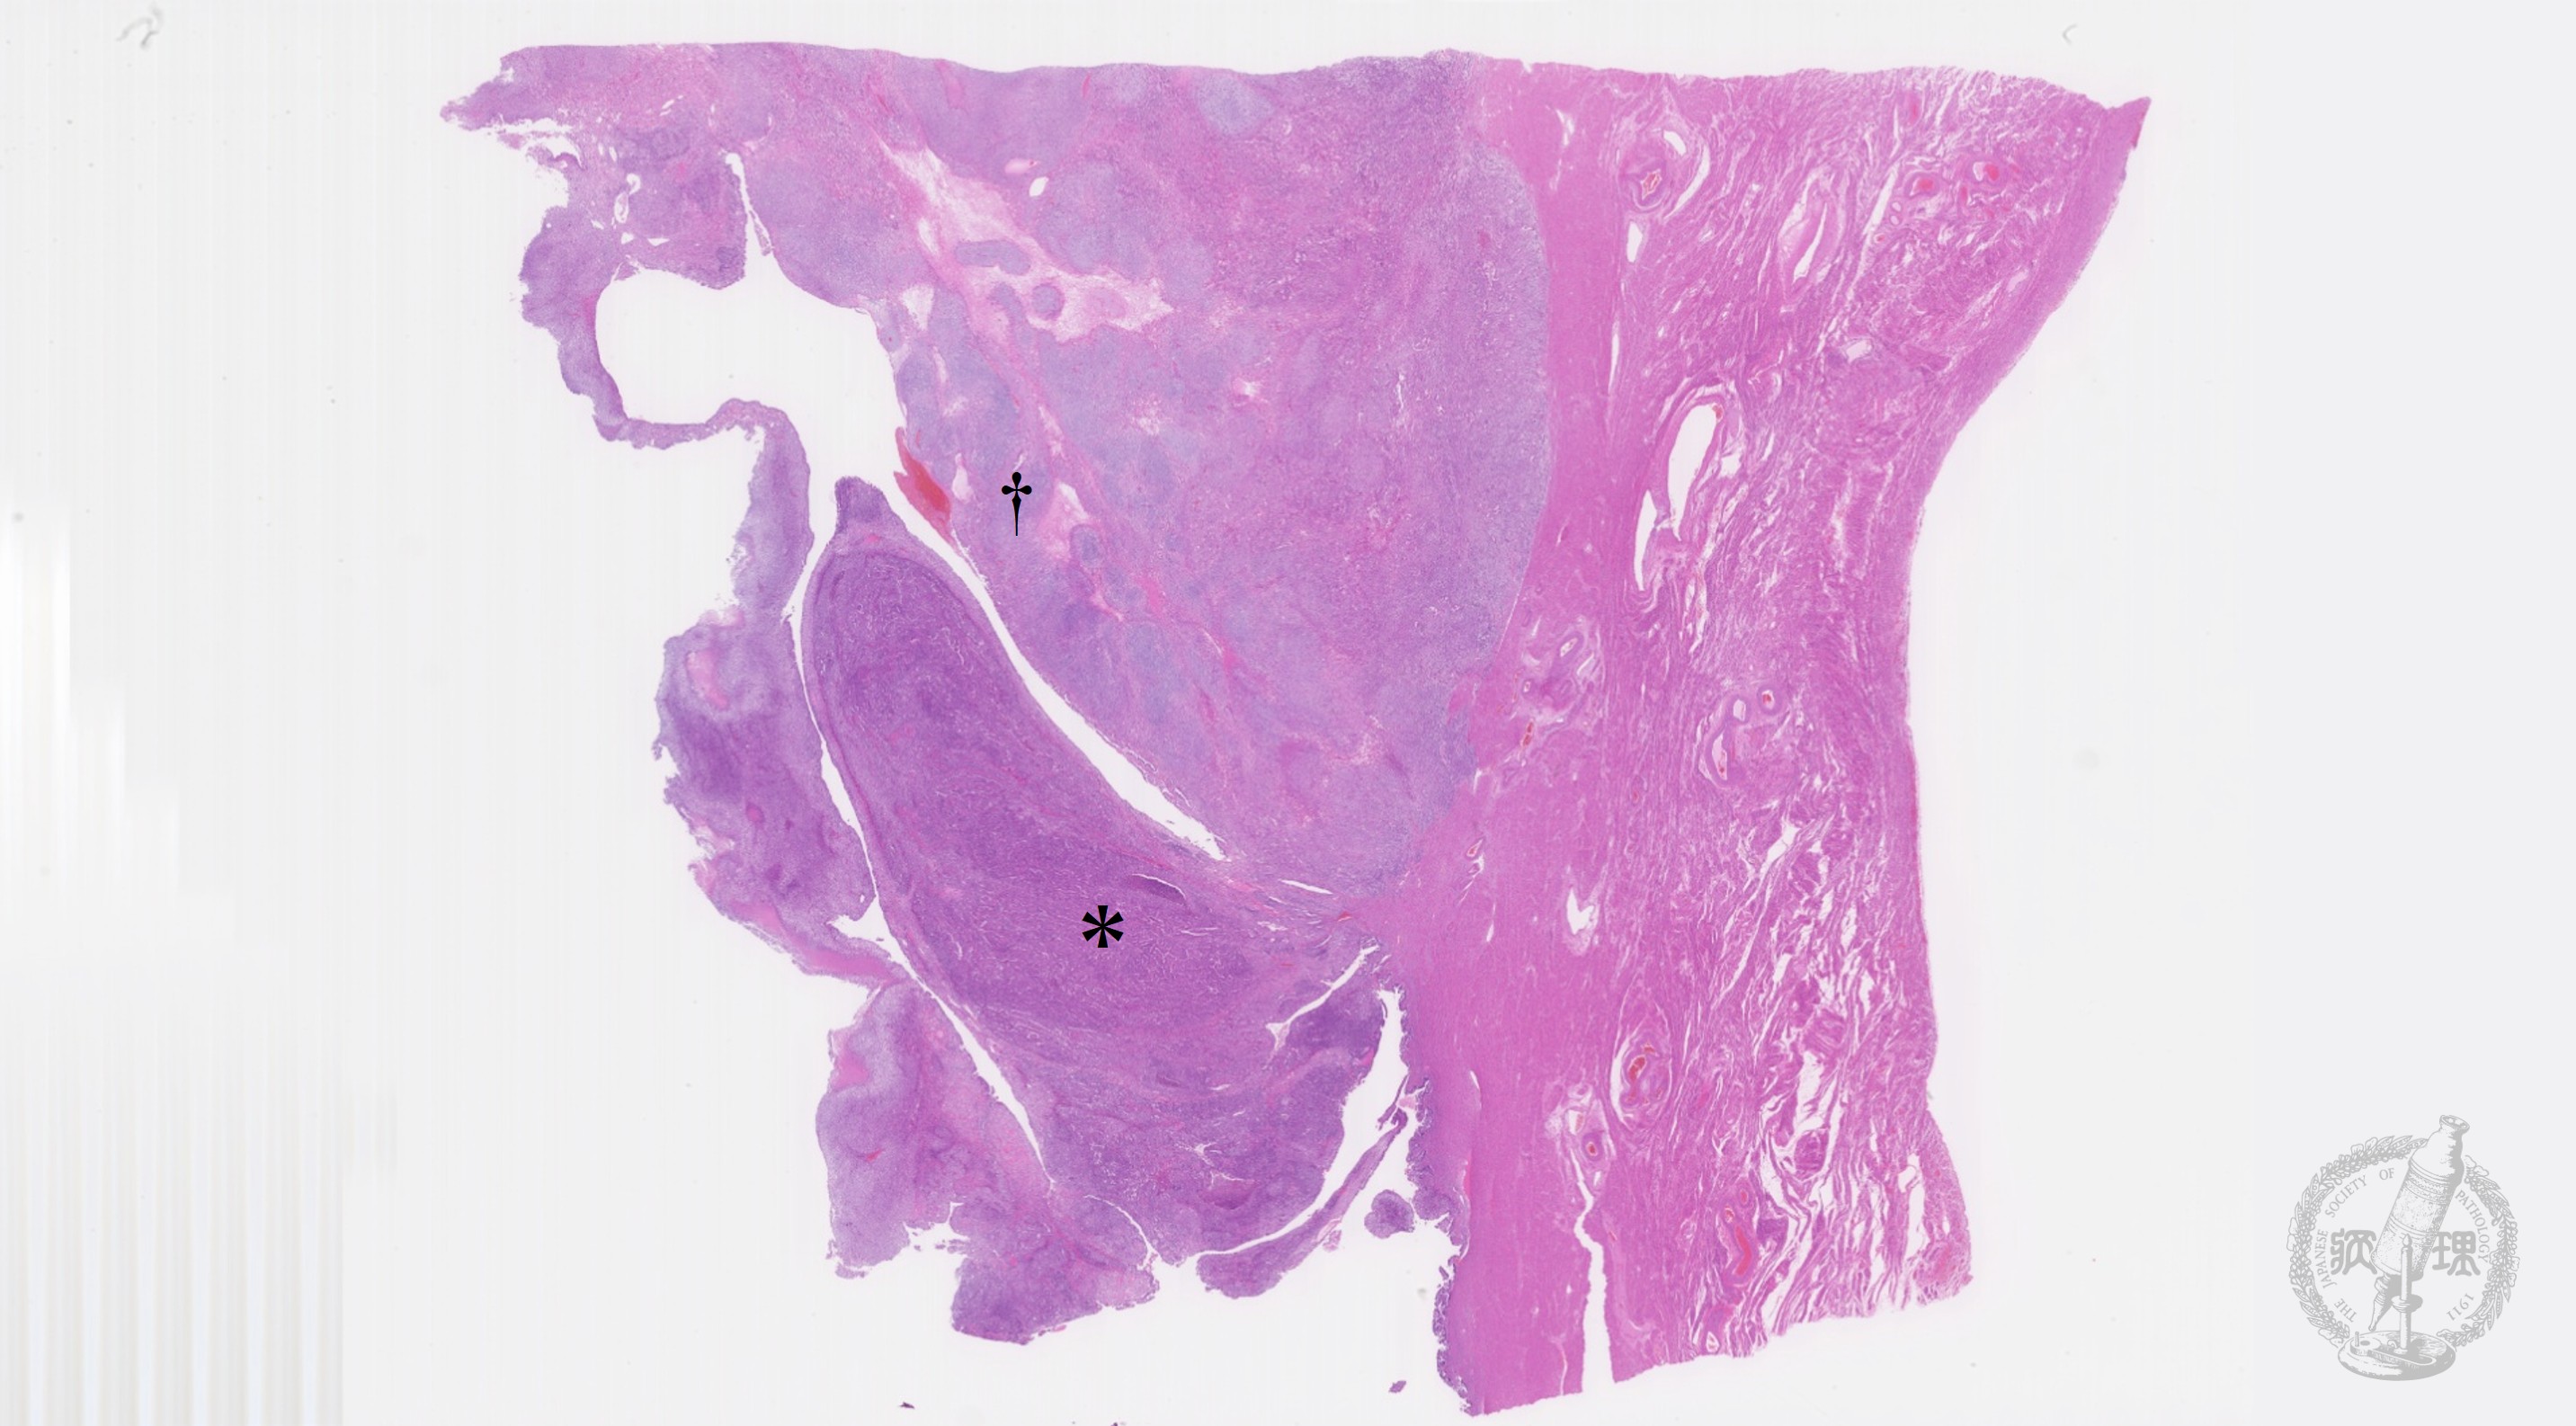

卵巣漿液性嚢胞腺腫マクロ像(未固定新鮮標本)

マクロ像(未固定新鮮標本):卵巣漿液性嚢胞腺腫。嚢胞内腔面は平滑で、充実性の増殖はみられない。

• 卵巣漿液性嚢胞腺腫マクロ像(未固定新鮮標本)